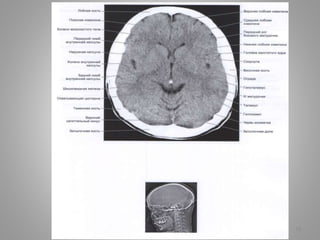

Деякі особливості КТ

79

• Ширина шлуночків і

поверхневого САП

поступово

збільшується з віком.

• Оскільки головний

мозок дитини

заповнює порожнину

черепа цілком,

зовнішній САП ледве

візуалізується.

• З віком борозни

розширюються, і СМР

стає помітнішою між

корою головного

мозку і склепінням

черепа.

• У деяких пацієнтів це фізіологічне зменшення

об'єму кори особливе помітно в лобових

долях.

• Простір між ними і лобовою кісткою стає

досить великим.

• Ця так звана лобова «інволюція головного

мозку" не повинна помилково вважатися

патологічною атрофією мозку або

природженою мікроцефалією.

• Якщо КТ-сканування, зображене на

малюнку було виконане літньому

пацієнтові, дослідник повинен був

би разцінити згладжені звивини,

як дифузний набряк головного

мозку.

• Перш ніж ставити діагноз набряку

чи атрофії головного мозку, ви

завжди повинні звернути увагу на

вік пацієнта.